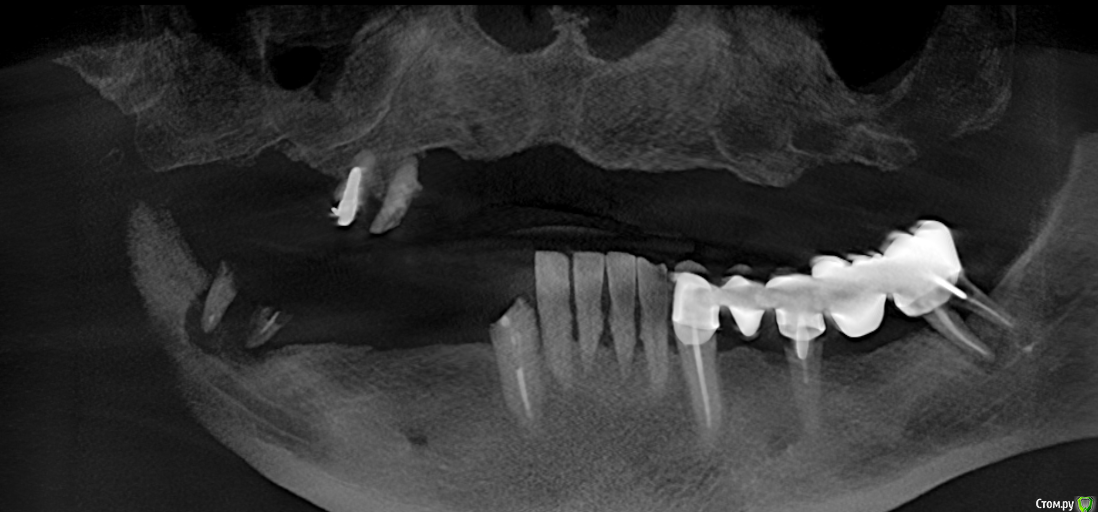

kamranchick Опубликовано 25 августа, 2017 Поделиться Опубликовано 25 августа, 2017 Планируется на днях работа, дилеры забыли прислать временные имплантаты...Планируется 6 имплантатов.Договорился с ортопедом сделать сьемный протез через несколько дней...как считаете лучше, сделать на фдмках протез, либо вокруг формирователей чтобы давление было. Ссылка на комментарий

kamranchick Опубликовано 27 августа, 2017 Автор Поделиться Опубликовано 27 августа, 2017 (изменено) Везде по 25 получил Изменено 27 августа, 2017 пользователем kamranchick Ссылка на комментарий

АнтонТЛТ Опубликовано 28 августа, 2017 Поделиться Опубликовано 28 августа, 2017 Чтобы облегчить жизнь ортопеду, можно было резецировать кость и ставить имплантаты по одному уровню 1 Ссылка на комментарий

kamranchick Опубликовано 29 августа, 2017 Автор Поделиться Опубликовано 29 августа, 2017 Чтобы облегчить жизнь ортопеду, можно было резецировать кость и ставить имплантаты по одному уровнюдумаю резорбирируется со временем, и будут на одном уровне)) Ссылка на комментарий